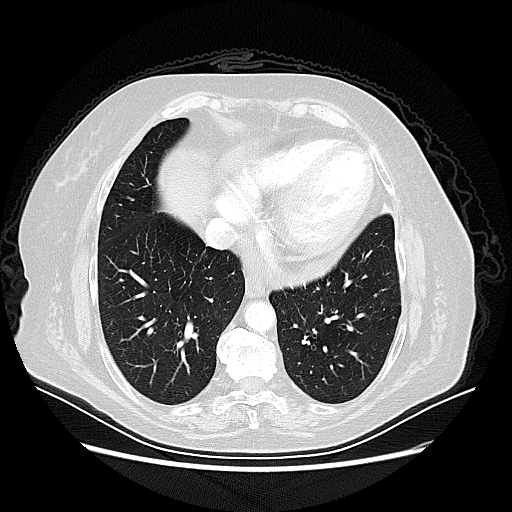

Targeted Slice 70 - Lung Window Analysis (Generated vs Real Venous)

0.633

Lung SSIM

140.5

Lung RMSE

104.3

Lung MAE

Average Lung Window Metrics Across All Slices (101 slices) - Generated vs Real Venous

0.620

Lung SSIM (Avg)

134.9

Lung RMSE (Avg)

104.4

Lung MAE (Avg)

Generated VENOUS CT scan (A→B translation)

Lung window (WL -600, WW 1500 β†’ Low βˆ’1350, High +150)